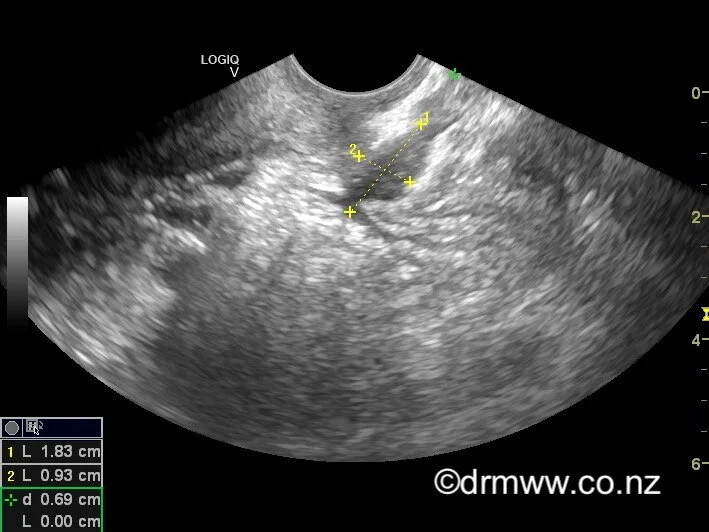

Rectal Muscularis Endometriosis nodule seen on TVUS